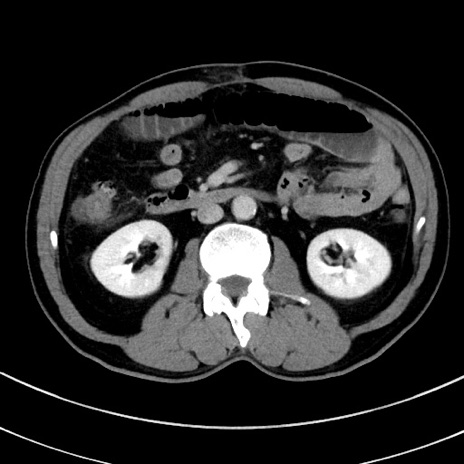

冠状断像

【症例】 60歳代男性

【主訴】 黒色吐物

【現病歴】 4日前から嘔気自覚、2日前の朝食後にも嘔気あり、自分で手で嘔吐反射起こし嘔吐したところ血が混ざっていたため受診。

【既往歴】 5年前汎発性腹膜炎を伴う急性虫垂炎で手術、高血圧、前立腺肥大症、高脂血症

【身体所見】 腹部正中に手術癩痕あり 腹部平坦・軟圧痛なし膨満感あり

【データ】WBC 8400、CRP 4.54